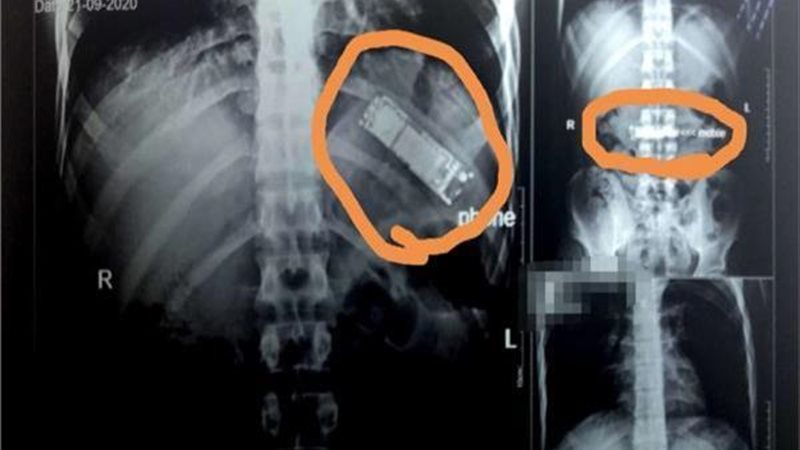

أغرب من الخيال.. رجل يبتلع هاتفا محمولا ويستقر في معدته

فى واقعة غريبة من نوعها وأغرب من الخيال وهى أن تصادف رجلا ابتلع هاتف محمول حيث تمكن رجل بطريقة ما من ابتلاع هاتف، وحسبما نشرت صحيفة "ذا مترو" البريطانية قام جميع الأطباء في كوسوفو على مساعدة الرجل المجهول البالغ من العمر 33 عامًا بعد أن استقر الهاتف في معدته. وكان حجمه أكبر من أن يستوعبه، كما كان يعرض حياته للخطر، حيث يمكن أن يتسرب حمض البطارية المتآكل. ونشر إسكندر تيلجاكو، الذي قاد الفريق الطبي، صوراً على “فيسبوك” للهاتف بعد إزالته، وكذلك صور الأشعة السينية والمنظار الداخلي أثناء وجوده بالداخل. وتمكن من إزالة الجسم الغريب دون قطع المعدة عن طريق إخراجه إلى ثلاث قطع بالمنظار، وقال إنه لم تكن هناك تعقيدات في إخراجه. وبحسب وسائل الإعلام المحلية، نقل الرجل نفسه إلى مستشفى في بريشتينا لأنه كان يعاني ألما من ابتلاع الشيء. وفقًا للجمعية البريطانية لأمراض الجهاز الهضمي، فإن معظم الأجسام الغريبة التي يبتلعها الناس تمر تلقائيًا، ولكن 10-20٪ من الحالات تتطلب إزالة بالمنظار وما يصل إلى 1٪ قد تتطلب الاستخراج الجراحي أو علاج المضاعفات وقالوا إن العملات المعدنية والأزرار والأشياء البلاستيكية والبطاريات والعظام كانت أشياء شائعة يتم ابتلاعها.